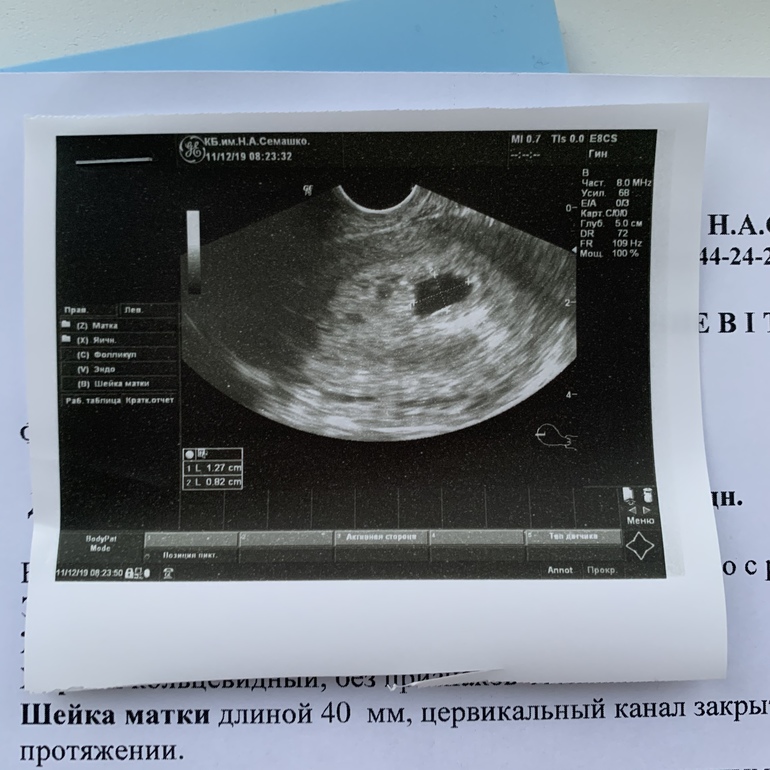

5 недель по узи ❤️

Врач сказала, что подросли конкретно за 10 дней!) желточный мешочек видно прекрасно!)

Нет, сказали

что оно должно быть круглое по книжке если, но бывает разное. Тонуса нет и это главное. Я тоже видела все узи на большом экране, оно в форме фасолинки я бы сказала)